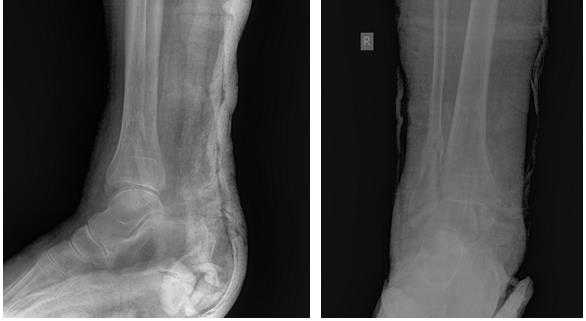

Пациентка Т. 80 лет. Травма за 3 недели до обращения, получила перелом обеих лодыжек правой голени со смещением, подвывихом стопы кнаружи. Обратилась в РТП, выполнена рентгенография, наложена гипсовая повязка. В связи с сохраняющимся выраженным отёком и болевым синдромом обратилась в клинику К+31.

На рентгенограммах в гипсе определяется значительный подвывих таранной кости кнаружи, консолидирующийся перелом нижней трети малоберцовой кости.